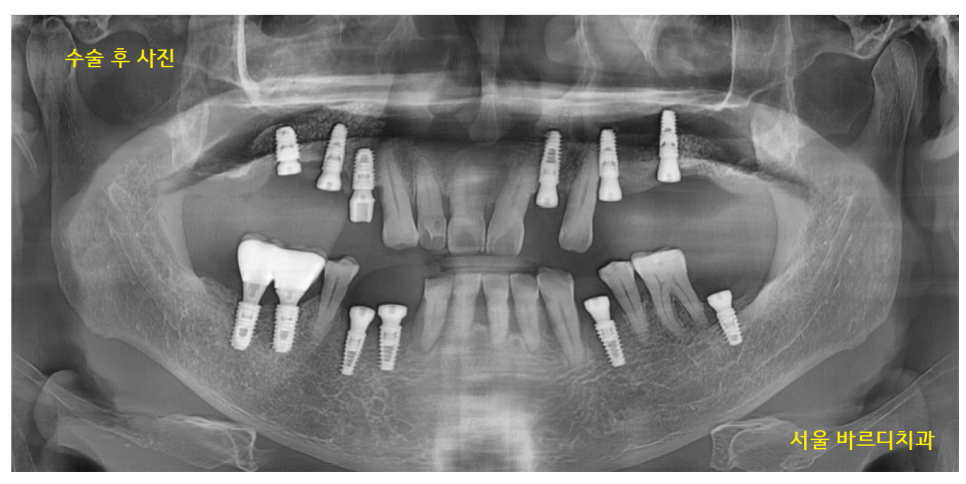

23.07.26

하남시청치과에서 수술을 완료한 사진입니다.